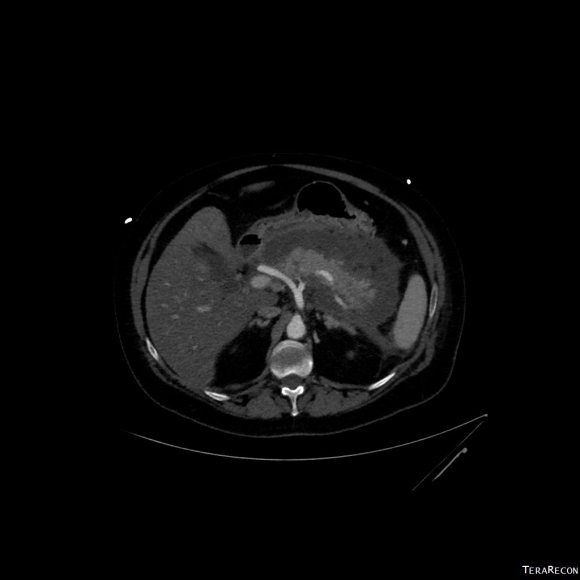

CT scan was performed showing an enlarging AAA over 8am and abundant retroperitoneal pancreatic fluid without abscess or infection. The AAA was infrarenal but complicated by a severely tortuous, short infrarenal neck with 90 degrees of angulation and about 8mm in length. As the pancreatic leak was yet early in the process, no pseudo aneurysms had formed. MRCP showed no active leak.